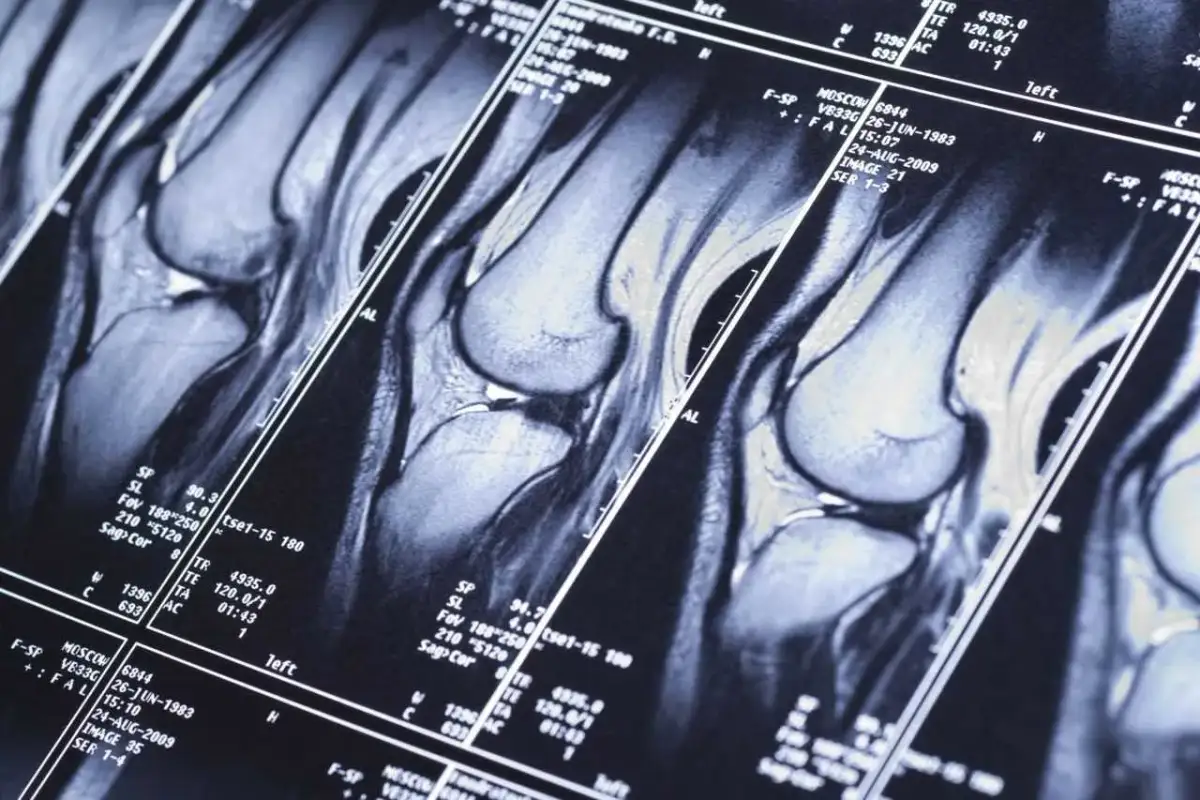

Neurologowie są szczególnie istotni w diagnostyce problemów związanych z układem nerwowym. Ich zadaniem jest ocena, czy objawy pacjenta wymagają przeprowadzenia badania MRI, które może pomóc w zdiagnozowaniu takich schorzeń jak stwardnienie rozsiane, guzy mózgu czy udary. Ortopedzi, z kolei, zajmują się diagnozowaniem schorzeń układu ruchu, takich jak urazy stawów czy choroby zwyrodnieniowe, i również mogą wystawić skierowanie na rezonans, aby dokładniej ocenić stan pacjenta. Neurochirurdzy, mając na celu diagnozowanie i leczenie schorzeń mózgu i rdzenia kręgowego, również są uprawnieni do wystawiania takich skierowań.Neurolog jako kluczowy specjalista w diagnostyce MRI

Ortopedzi są specjalistami zajmującymi się diagnostyką i leczeniem schorzeń układu ruchu, takich jak urazy stawów, złamania czy choroby zwyrodnieniowe. W przypadku pacjentów z problemami bólowymi w obrębie stawów lub kręgosłupa, ortopeda może zlecić wykonanie rezonansu magnetycznego, aby dokładniej ocenić stan tkanek miękkich, takich jak chrząstka czy więzadła. To badanie jest szczególnie przydatne w diagnozowaniu uszkodzeń, które nie są widoczne na standardowych zdjęciach rentgenowskich.

Neurochirurdzy, z kolei, specjalizują się w leczeniu schorzeń mózgu i rdzenia kręgowego. Ich rola w kierowaniu na badania MRI jest kluczowa, szczególnie w przypadkach podejrzenia guza mózgu, krwawienia wewnętrznego czy innych poważnych patologii. Rezonans magnetyczny dostarcza neurochirurgom niezbędnych informacji, które pomagają w planowaniu operacji oraz ocenie skutków leczenia.